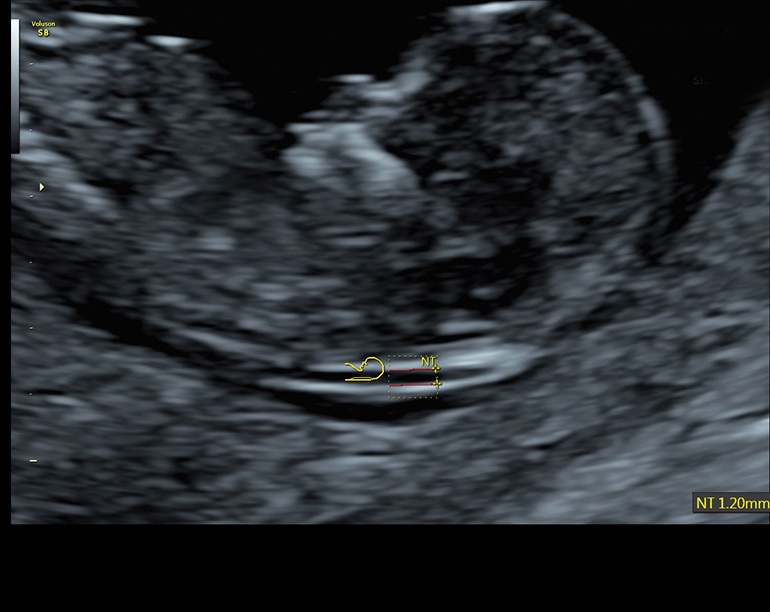

• Стандартизованные измерения толщины воротникового пространства и IV желудочка головного мозга плода в I триместре беременности (SonoNT и SonoIT): Эти технологии позволяют в полуавтоматическом режиме измерять толщину воротникового пространства и размеры желудочка головного мозга плода в первом триместре беременности, что помогает в ранней диагностике возможных аномалий.

• Автоматический расчет толщины воротникового пространства SonoNT и размера четвертого желудочка SonoIT